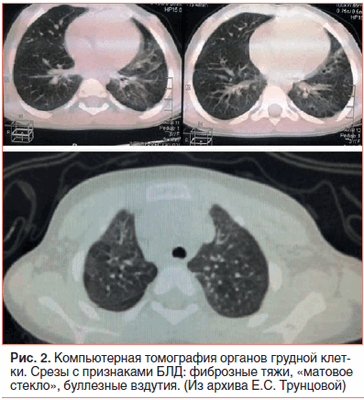

Выставлен диагноз: Глубокая недоношенность (26 нед. гестации). БЛД недоношенных, новая форма, тяжелой степени тяжести, дыхательная недостаточность II степени. ВПС: ОАП, сердечная недостаточность IIА стадии, ФК II, малая аномалия развития сердца: открытое овальное окно. Последствия гипоксического поражения ЦНС, синдром угнетения. Ранняя анемия недоношенных средней степени тяжести. Ретинопатия сетчатки обоих глаз III стадии, активная фаза.

Далее на фоне лечения и положительной клинико-лабораторной динамики (прирост весоростовых показателей, отсутствие воспалительных изменений в гемограмме, отрицательные показатели СРБ и ПКТ, отсутствие патологических отклонений остальных биохимических показателей, улучшение показателя SaО2: 94–95%) на 65-й день жизни ребенок был экстубирован и переведен на самостоятельное дыхание. Ингаляционная терапия по поводу тяжелой БЛД ИГКС (будесонидом) была продолжена в прежнем объеме.

Амбулаторно ребенок наблюдался у педиатра, пульмонолога, кардиолога с диагнозом: Бронхолегочная дисплазия недоношенных, новая форма, тяжелой степени тяжести, осложненная вторичной высокой легочной гипертензией (89 мм рт. ст.). Состояние после коррекции ВПС (лигирование ОАП, АМПП, открытое овальное окно, эктопическая хорда в полости левого желудочка). Парез левой голосовой связки. Последствия гипоксического поражения ЦНС. Задержка физического и моторного развития. Ретинопатия сетчатки обоих глаз III стадии, активная фаза (оперативное лечение: транспупиллярная лазеркоагуляция сетчатки). Анемия недоношенных средней степени. Белково-энергетическая недостаточность III степени.

На протяжении первого года жизни ребенок имел крайне низкое физическое развитие, дисгармоничное за счет дефицита массы (в 1 год масса 6,0 кг и длина тела 58 см) -6,2SD и -3,2SD по росту и массе соответственно [17]. Обращали на себя внимание повышенная слабость, утомляемость, сухой кашель в течение дня, периодически стридорозное дыхание, одышка в покое смешанного характера от 65 дыхательных движений в минуту в покое, ремиссии и до 82 в минуту в периоды обострения БЛД. Сатурация кислородом в периферической крови при пульсоксиметрии составляла 90–95%. За период наблюдения наиболее тяжелое ухудшение состояния отмечалось дважды в возрасте 6 мес. и 8 мес., что было связано с респираторными инфекциями.

На фоне лечения отмечена положительная динамика СДЛА с 89 до 46 мм рт. ст., клинические признаки ЛАГ значительно уменьшились, сохраняются признаки БЛД и последствия гипоксического поражения ЦНС, задержки физического и психомоторного развития, перенесенной коррекции ВПС.

Таким образом, данный клинический случай демонстрирует развитие легочной гипертензии на фоне БЛД и врожденного порока сердца у ребенка с экстремально низкой массой тела. Авторы пытались акцентировать внимание педиатров, детских кардиологов и пульмонологов на проблеме ЛАГ, которая расценивалась как вторичная, ассоциированная с двумя основными тяжело протекающими заболеваниями. На фоне комплексного адекватного лечения БЛД, своевременной коррекции ВПС (ОАП) и терапии ЛАГ (силденафилом) к концу первого года жизни наступила положительная динамика в течении БЛД, врожденного порока сердца, в физическом развитии ребенка, и ЛАГ приобрела стабильное течение с тенденцией к дальнейшему снижению СДЛА.